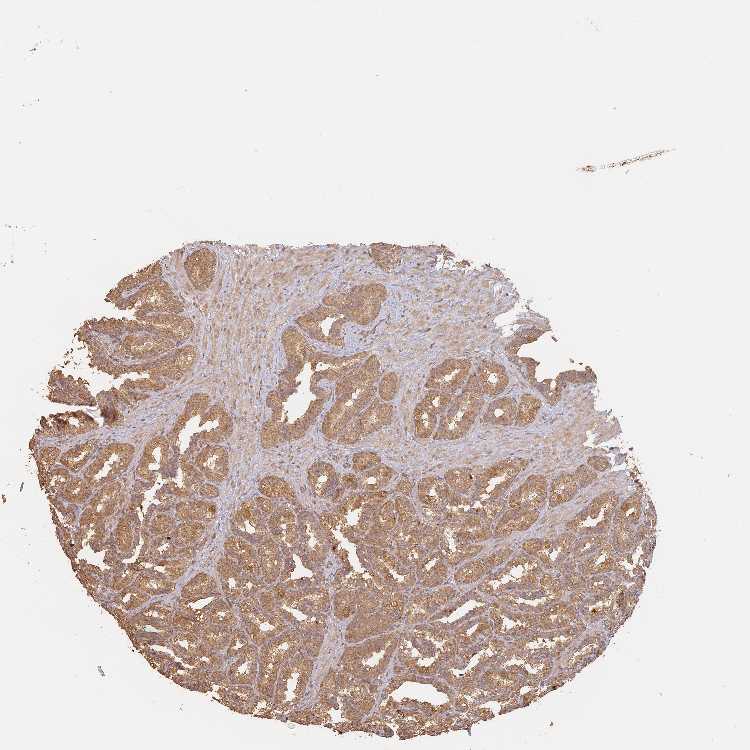

SEMINAL VESICLE - Antibody stainingi

Antibody staining in the annotated cell types in the current human tissue is reported as not detected, low, medium, or high, based on conventional immunohistochemistry profiling in selected tissues. This score is based on the combination of the staining intensity and fraction of stained cells.

Each image is clickable and will lead to virtual microscopy that enables deeper exploration of all samples and also displays staining intensity scores, fraction scores and subcellular localization as well as patient and tissue information for each sample.

Antibody HPA041019Antibody HPA042033

Glandular cells LowMedium